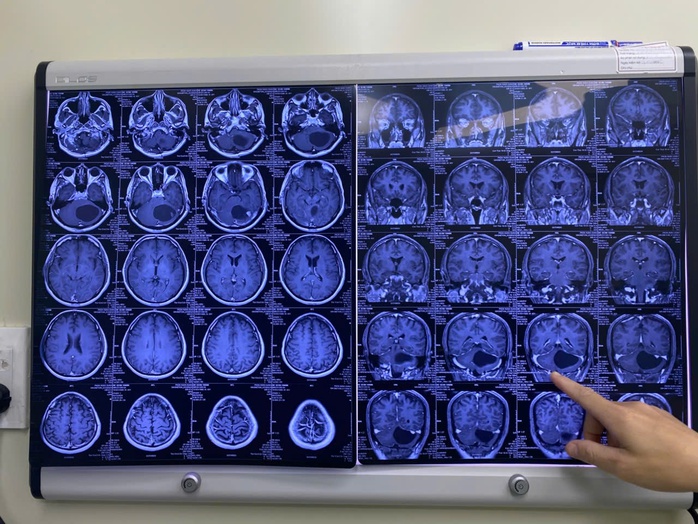

Ảnh chụp khối u to bằng quả trứng vịt của bệnh nhân

Theo BSCKII Đỗ Văn Long, Bệnh viện Đa khoa Quốc tế Minh Anh (người trực tiếp mổ), tiểu não vốn nhỏ bé nhưng ở bệnh nhân này lại chứa một khối u to bằng quả trứng vịt, chèn ép trực tiếp vào thân não – nơi điều khiển mọi hoạt động sống còn của cơ thể. Chỉ cần một tích tắc sơ sẩy hoặc khối u lớn thêm chút nữa, bệnh nhân có thể tử vong đột ngột.

Khó khăn của ca bệnh này không chỉ nằm ở kích thước khối u mà còn ở bản chất của nó: U nguyên bào mạch máu thường "ngốn" máu rất dữ dội và nằm sát các cấu trúc thần kinh trung ương. Một sơ suất nhỏ có thể gây chảy máu ồ ạt, dẫn đến di chứng liệt toàn thân hoặc tử vong ngay trên bàn mổ.